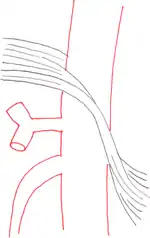

Further evaluation and confirmation can be obtained via angiography to investigate the anatomy of the celiac artery.[5] Historically, conventional angiography was used, although this has been largely replaced by less invasive techniques such as computed tomography (CT) and magnetic resonance (MR) angiography.[2][5] Because it provides better visualization of intra-abdominal structures, CT angiography is preferred to MR angiography in this setting.[5] The findings of focal narrowing of the proximal celiac artery with poststenotic dilatation, indentation on the superior aspect of the celiac artery, and a hook-shaped contour of the celiac artery support a diagnosis of MALS.[2] These imaging features are exaggerated on expiration, even in normal asymptomatic individuals without the syndrome.[2]

Proximal celiac artery stenosis with poststenotic dilatation can be seen in other conditions affecting the celiac artery.[2] The hook-shaped contour of the celiac artery is characteristic of the anatomy in MALS and helps distinguish it from other causes of celiac artery stenosis such as atherosclerosis.[2] This hooked contour is not entirely specific for MALS however, given that 10–24% of normal asymptomatic individuals have this anatomy.[2]

Median arcuate ligament syndrome-a)Stenosis and aneurysm of celiac artery because of compression arrows b)severe stenosis and poststenotic dilatation white arrow c) median arcuate ligaments arrows and gastric mucasal thickening -

Coeliacus compression